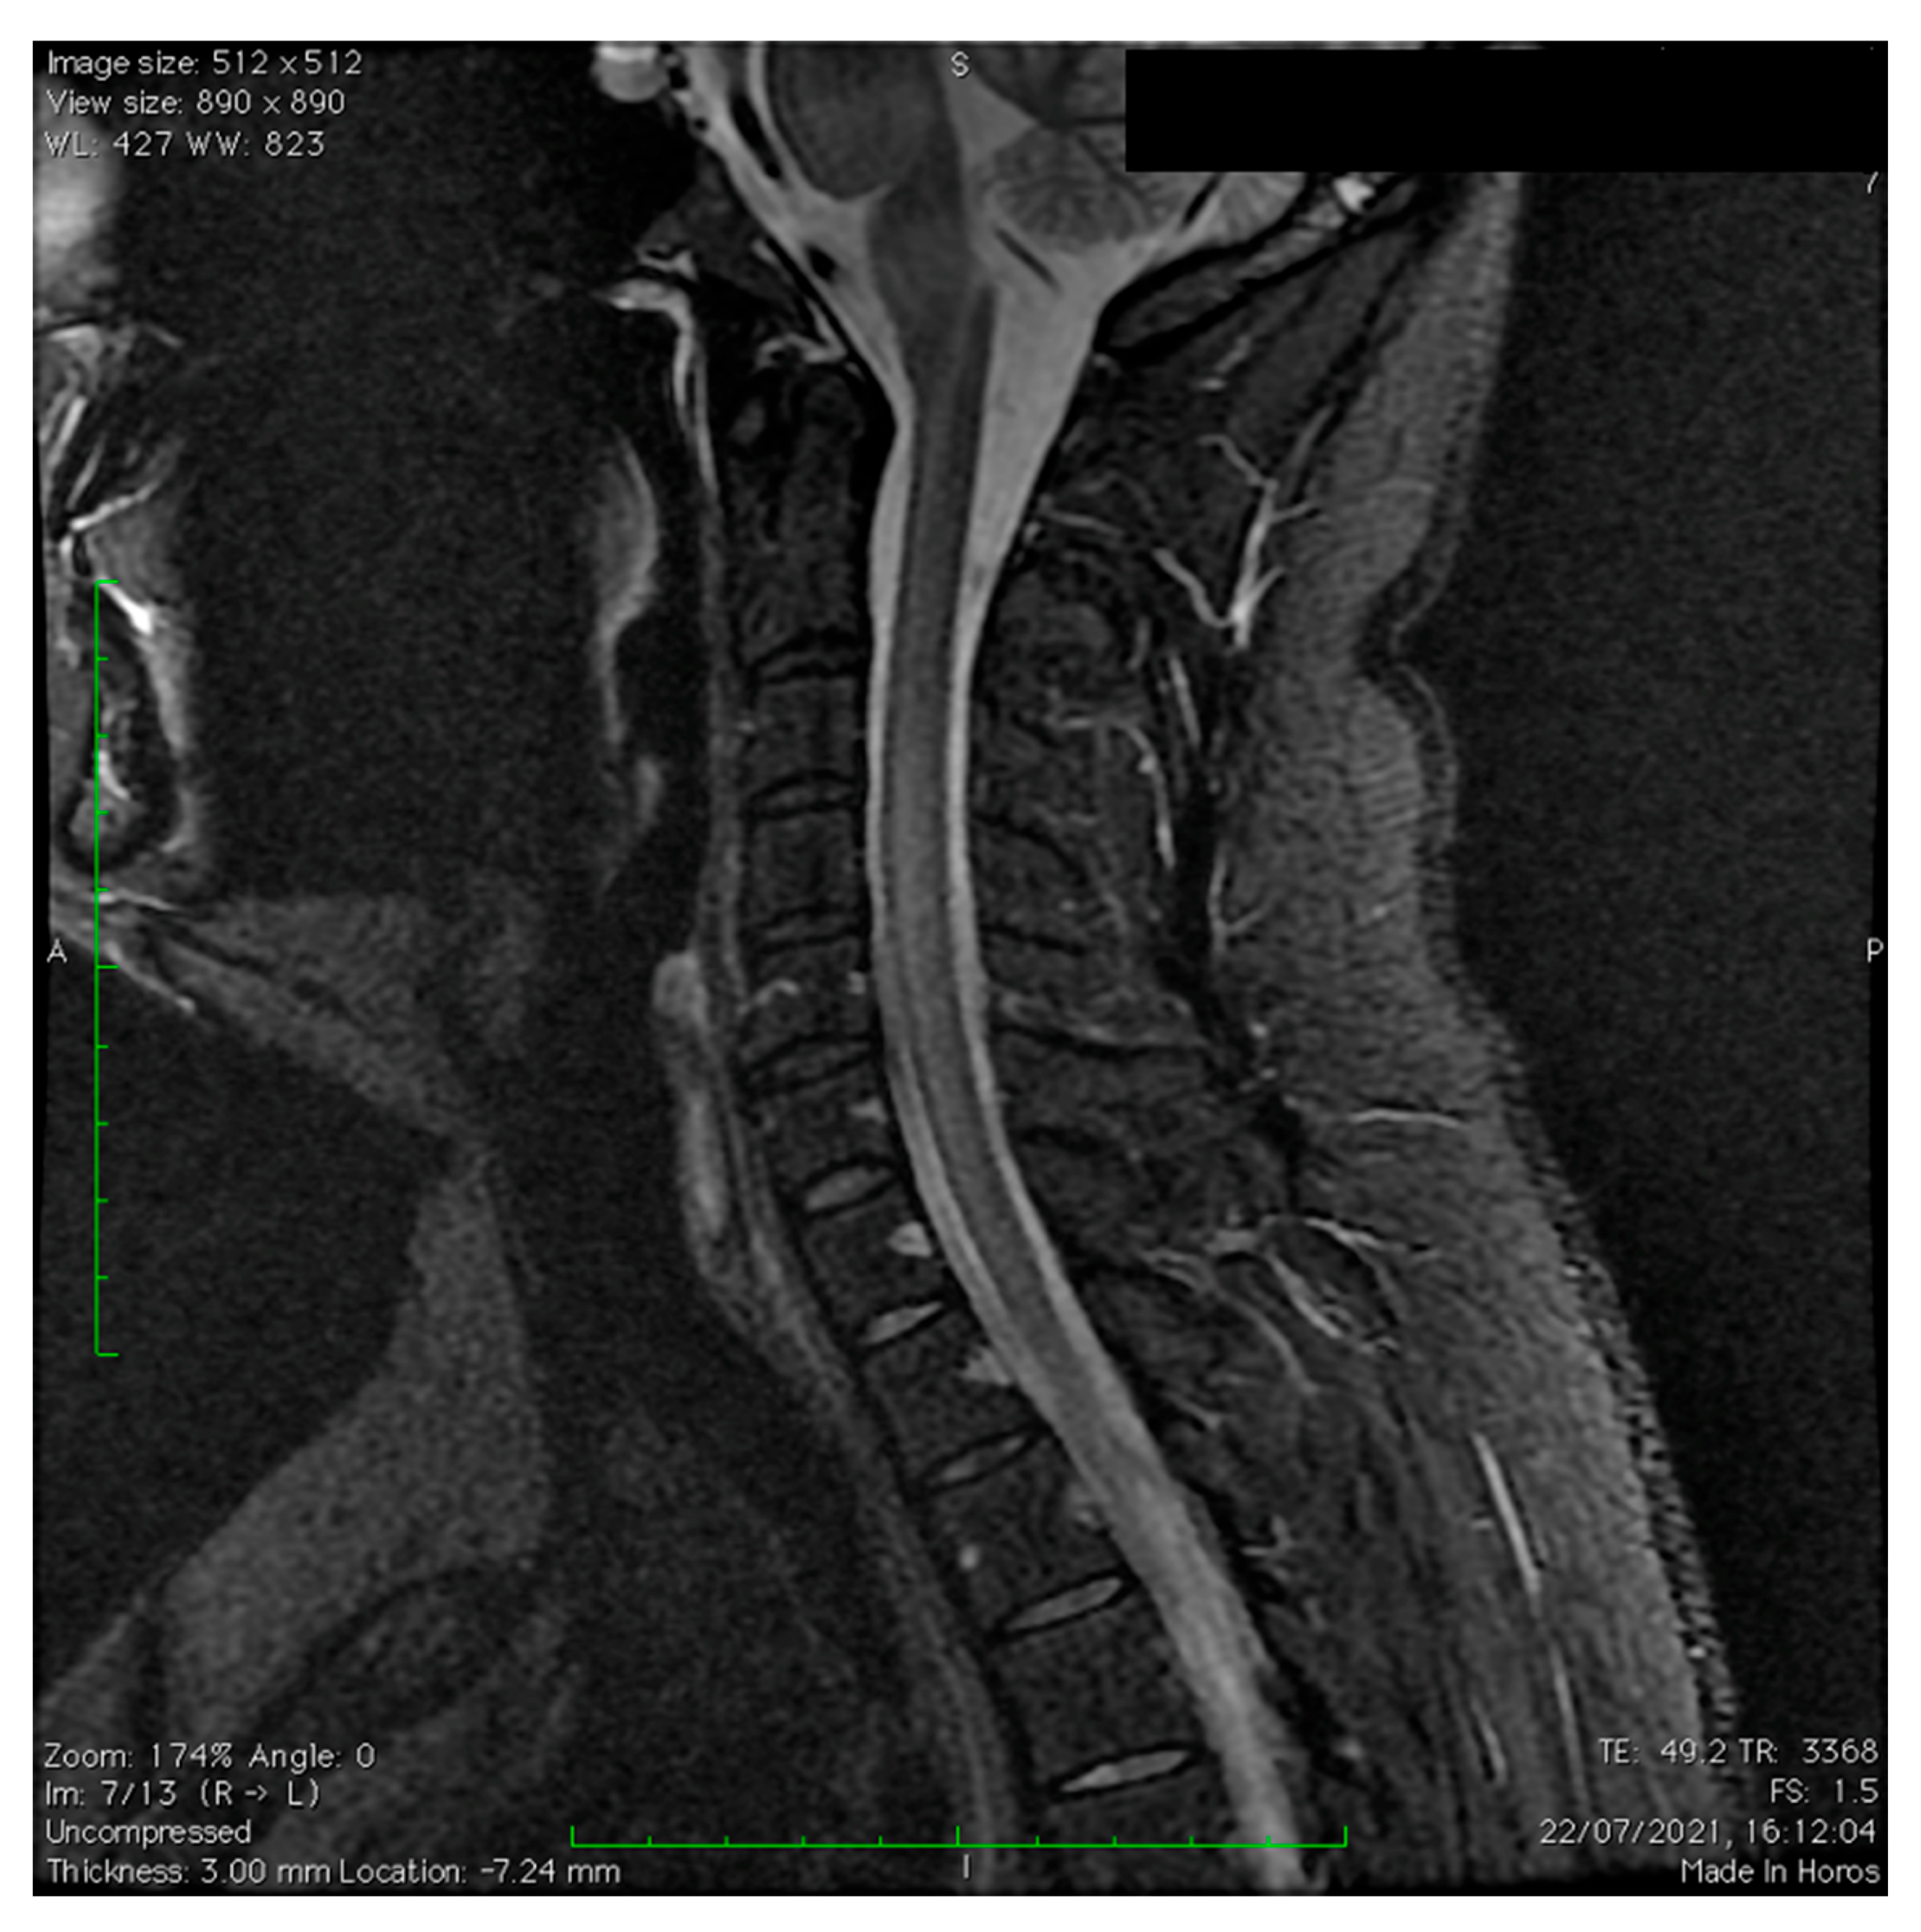

3.1. Our Clinical Experience

- Appearance on MRI images;

- Brain and/or spine MRI shows lesions in the acute phase (3 months).

- Brain lesions on MRI are diffuse and poorly demarcated and have the following characteristics:

- Large-size lesions of 1–2 cm that mainly affect the white matter.

- Hypointense T1 lesions affecting white matter are rare.